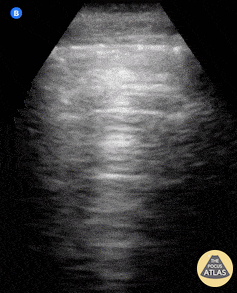

What is seen in this ultrasound?

Normal lung sliding and A-lines.

A-lines are defined as horizontal, hyperechoic reverberation artifacts that appear at regular intervals below the pleural line, representing normal air-filled lung parenchyma. The presence of both lung sliding and A lines is considered the normal sonographic pattern of a well-aerated lung